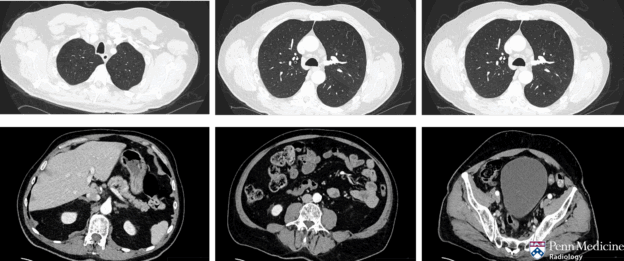

A 62-year-old man presented to the hospital with complaints of five months of dizziness and two months of altered mental status and impaired ability to ambulate, as well as recent weight loss.